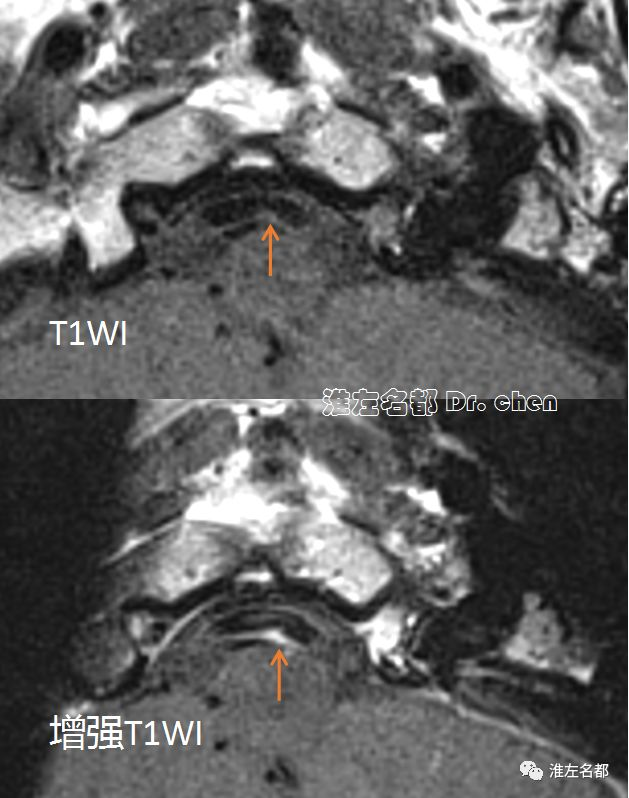

管壁高分辨MRI:右侧椎动脉颅内段局部管壁偏心增厚(橙箭),T2信号不均一(粥样硬化斑块),等T1信号,并显著偏心强化。